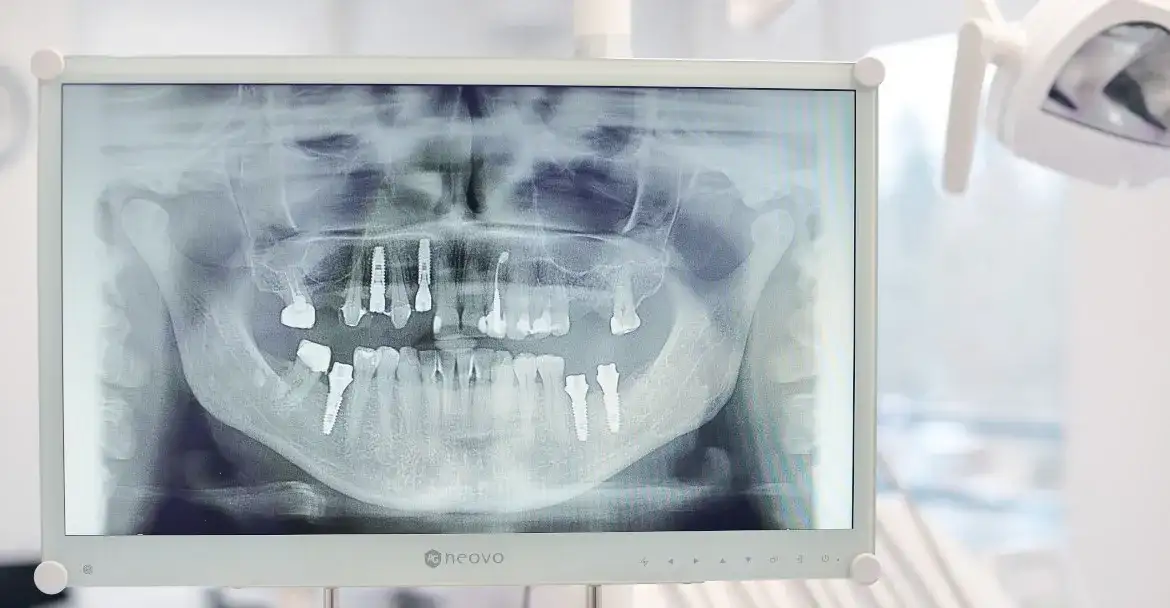

RTG zęba ujawnia ukrytą próchnicę, stany zapalne i torbiele. Sprawdź, co dentysta widzi na zdjęciu i dlaczego to klucz do zdrowego uśmiechu. Poznaj rodzaje RTG i bezpieczeństwo.